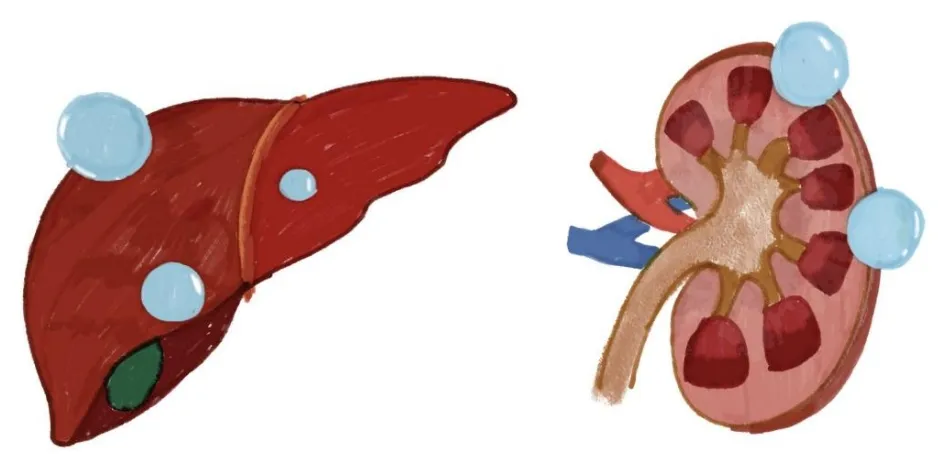

1、什么是肝肾囊肿?

这两个小家伙,一个藏在肝脏里,一个躲在肾脏中,平时悄无声息,很多时候都是在体检时偶然被发现。

肝肾囊肿其实是一种很常见的良性病变,发病率较高。大多数囊肿都比较小,不会引起任何症状,就像是身体里的“小水泡”。但是,当它们长大到一定程度时,就开始不甘寂寞,搞出一些小动作来刷存在感了。